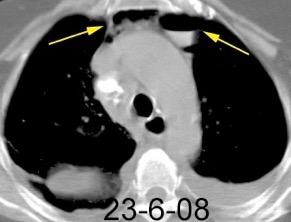

Hematoma retroesternal y pericárdico en cirugía de válvula mitral. Migración de suturas

Boiselle P.M.et al. Wandering wires: frequency of sternal wire abnormalities in patients with sternal dehiscence. AJR 1999;